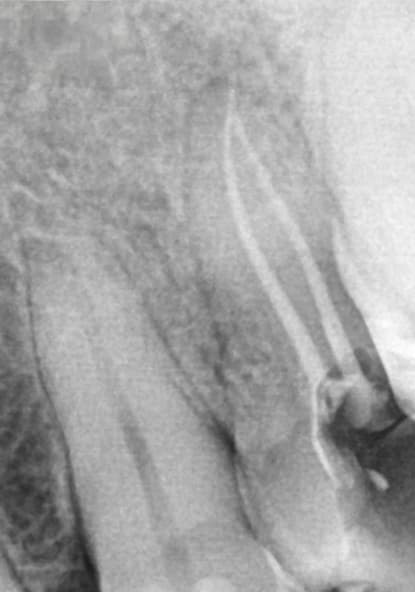

A 55-year-old patient presented for endodontic therapy with a diagnosis of irreversible pulpitis affecting a maxillary premolar. Radiographic assessment revealed partially calcified canal trajectories, suggesting chronic pulp inflammation (Figure 2). After conventional access and irrigation with Dual Rinse® (1.5% sodium hypochlorite [NaOCl] combined with a chelating agent compatible with NaOCl) (Medcem GmbH, medcem.eu), an EdgeOne Blaze Utopia R20 file was selected for canal preparation.

The file was introduced into the canal until initial resistance was encountered, then activated using a reciprocating motion in 1-mm increments. After each cycle, the instrument was removed and cleaned, and irrigation was repeated. This sequence progressively enlarged the coronal and middle thirds, facilitating apical access.

Working length was then determined using a #10 K-file and an apex locator. Subsequent anticurvature flaring with brushing motion further optimized canal geometry. This crown-down approach minimized instrument stress, improved irrigant exchange, and enhanced apical control.

Apical shaping was achieved through short, controlled movements and copious irrigation, reducing debris accumulation and apical blockage. The R20’s flexibility, variable taper, and cutting efficiency enabled precise shaping and easy cone fitting with F1-compatible gutta-percha (Figure 3).